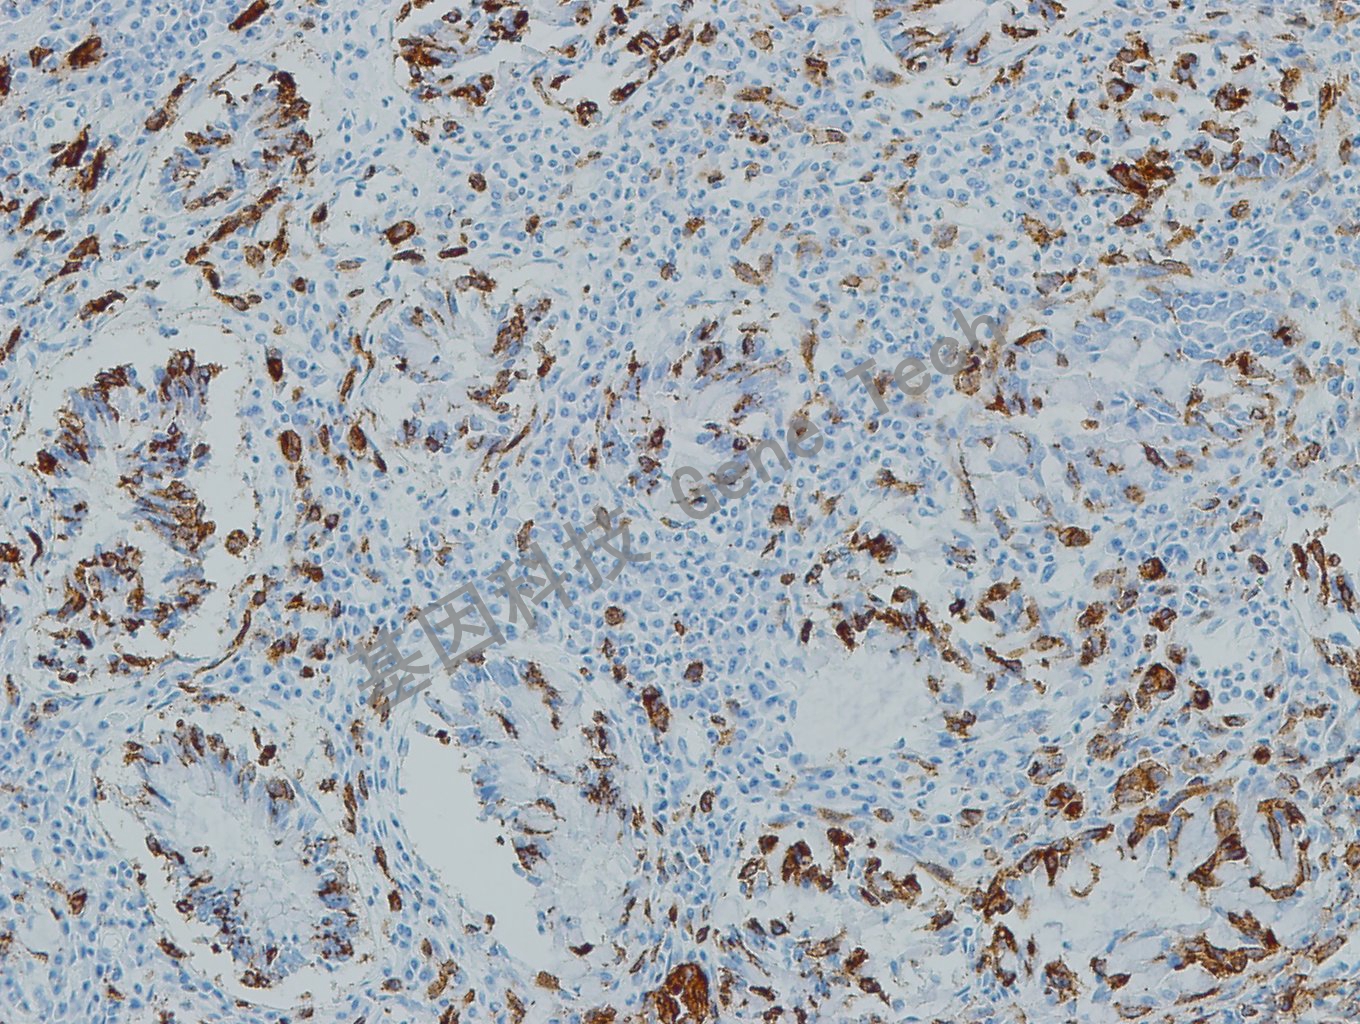

| 預(yù)處理:高pH熱修復(fù) | 陽(yáng)性部位:細(xì)胞漿 | 陽(yáng)性對(duì)照:黑色素瘤 |

| 簡(jiǎn)介:PNL2是針對(duì)黑色素細(xì)胞抗原的一種新型單抗,在正常黑色素細(xì)胞及其來(lái)源的腫瘤中呈細(xì)胞質(zhì)染色,其檢出陽(yáng)性率高于以往的標(biāo)記物。透明細(xì)胞瘤、血管平滑肌脂肪瘤和淋巴管平滑肌瘤可見(jiàn)不同程度的陽(yáng)性;血管周上皮樣細(xì)胞腫瘤和黑色素性神經(jīng)鞘瘤的非黑色素細(xì)胞病變區(qū)陽(yáng)性。與HMB45、MART-1、Tyrosinase和MiTF抗體聯(lián)合用于黑色素瘤和透明細(xì)胞肉瘤的診斷。 | ||

| 黑色素瘤石蠟切片,用 PNL2(GT2336)染色,細(xì)胞漿陽(yáng)性,DAB 顯色。 | ||